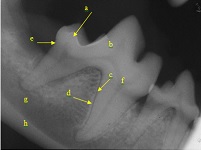

c

Abbreviation

Pathology

a

vertical bone resorption

b

horizontal bone resorption

loss of periodontal ligament space